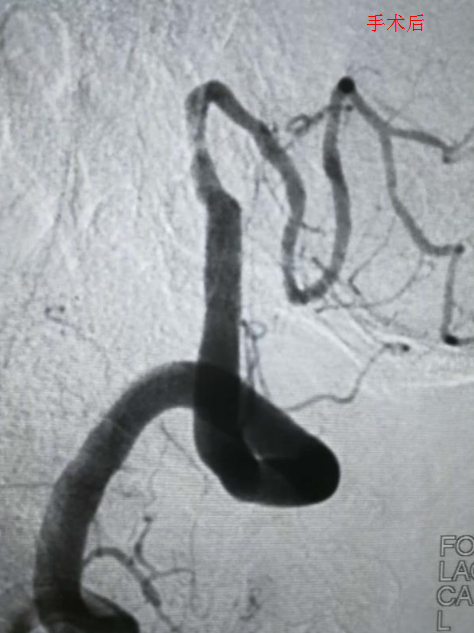

此时,南方医科大学深圳医院神经内科的学科带头人刘亚杰及其团队果断而及时的为病人选择了在介入下动脉支架取栓术。在惊心动魄、有条不紊的2个小时手术过程中,脑血管造影发现了闭塞的动脉血管,通过支架的方式撑开了闭塞的血管,接着再将堵塞血管的血栓拉出体外,闭塞的血管被打通,血流也恢复了供应。邹爷爷的神志恢复了正常,头晕很快就改善了,也转危为安。

刘亚杰介绍,诊断出病情的时候,邹爷爷发病已超过6小时,已经不适合静脉溶栓这一目前最有效的药物治疗方式。最新的卒中治疗指南建议,此时,应该对大脑动脉被大面积血栓堵塞的卒中患者行支架取栓,取出阻塞动脉血管的血栓。支架取栓是目前针对急性脑梗死最为有效的治疗方法,它是一种微创手术,通过支架将血栓直接从堵塞血管中取出,使闭塞血管快速再通,恢复大脑供血,降低患者的死亡率和致残率,改善患者以后的生活状态,可将血管开通率提高到80%。